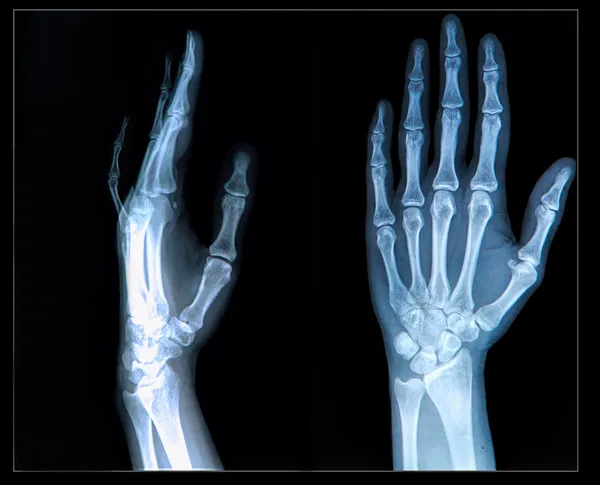

Кости предплечья относятся к длинным трубчатым костям . Их две: локтевая кость, ulna, лежащая медиально, и лучевая radius Локтевая кость, ulna . Верхний (проксимальный) утолщенный конец локтевой кости (эпифиз) разделяется на два отростка: задний, более . . .

Строение локтевого сустава .(1) плечевая кость, (2) лучевая кость,(3) локтевая кость, (4) эластичный хрящ, (5) синовиальная жидкость . Скелет кистей рук образован восемью костями запястья (1), пятью пястными костями (2), и фалангами пальцев (3) . Суставчики, соединяющие . . .

Локтевой сустав образован тремя костями - дистальной частью плечевой кости и проксимальными частями локтевой и лучевой костей . Локтевая кость имеет трехгранную форму . На верхнем, проксимальном, конце кости находится утолщение, на котором спереди . . .